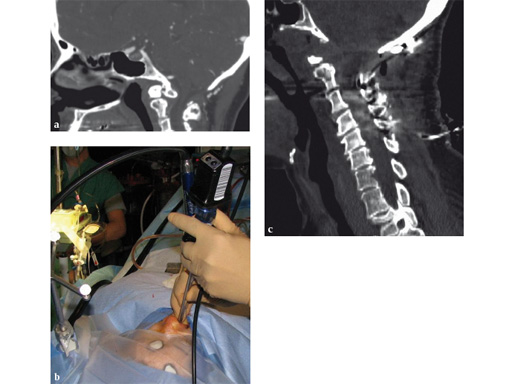

Placement of instrumentation in anatomy that has been distorted due to significant deformity or due to previous surgery and subsequent scarring and ossification can be difficult and is associated with an increased rate of misplacement. In these cases CAS allows precise placement of instrumentation even in the absence of regular anatomical landmarks (Fig 4).

Fig 4 In this cervical deformity case extensive ossification was present and regular landmarks not available. Navigation allowed precise placement of cervical pedicle screws.

Instrumentation of the cervical and thoracic spine can entail special challenges, even with open surgery and relatively straightforward anatomy. Screw placement with CAS can facilitate the placement of pedicle screws with very high precision (Figs 4, 8). A recent publication has demonstrated that for thoracic pedicle screws the use of CAS resulted in reduction in operative time and improvement in screw accuracy [14]. In the cervical spine placement of pedicle screws in patients has been accomplished with higher accuracy using 3-D-nav when compared to conventional techniques [15]. In the high cervical spine it can be used for accurate instrumentation of the occiput, C1 and C2 (Fig 9) [16].